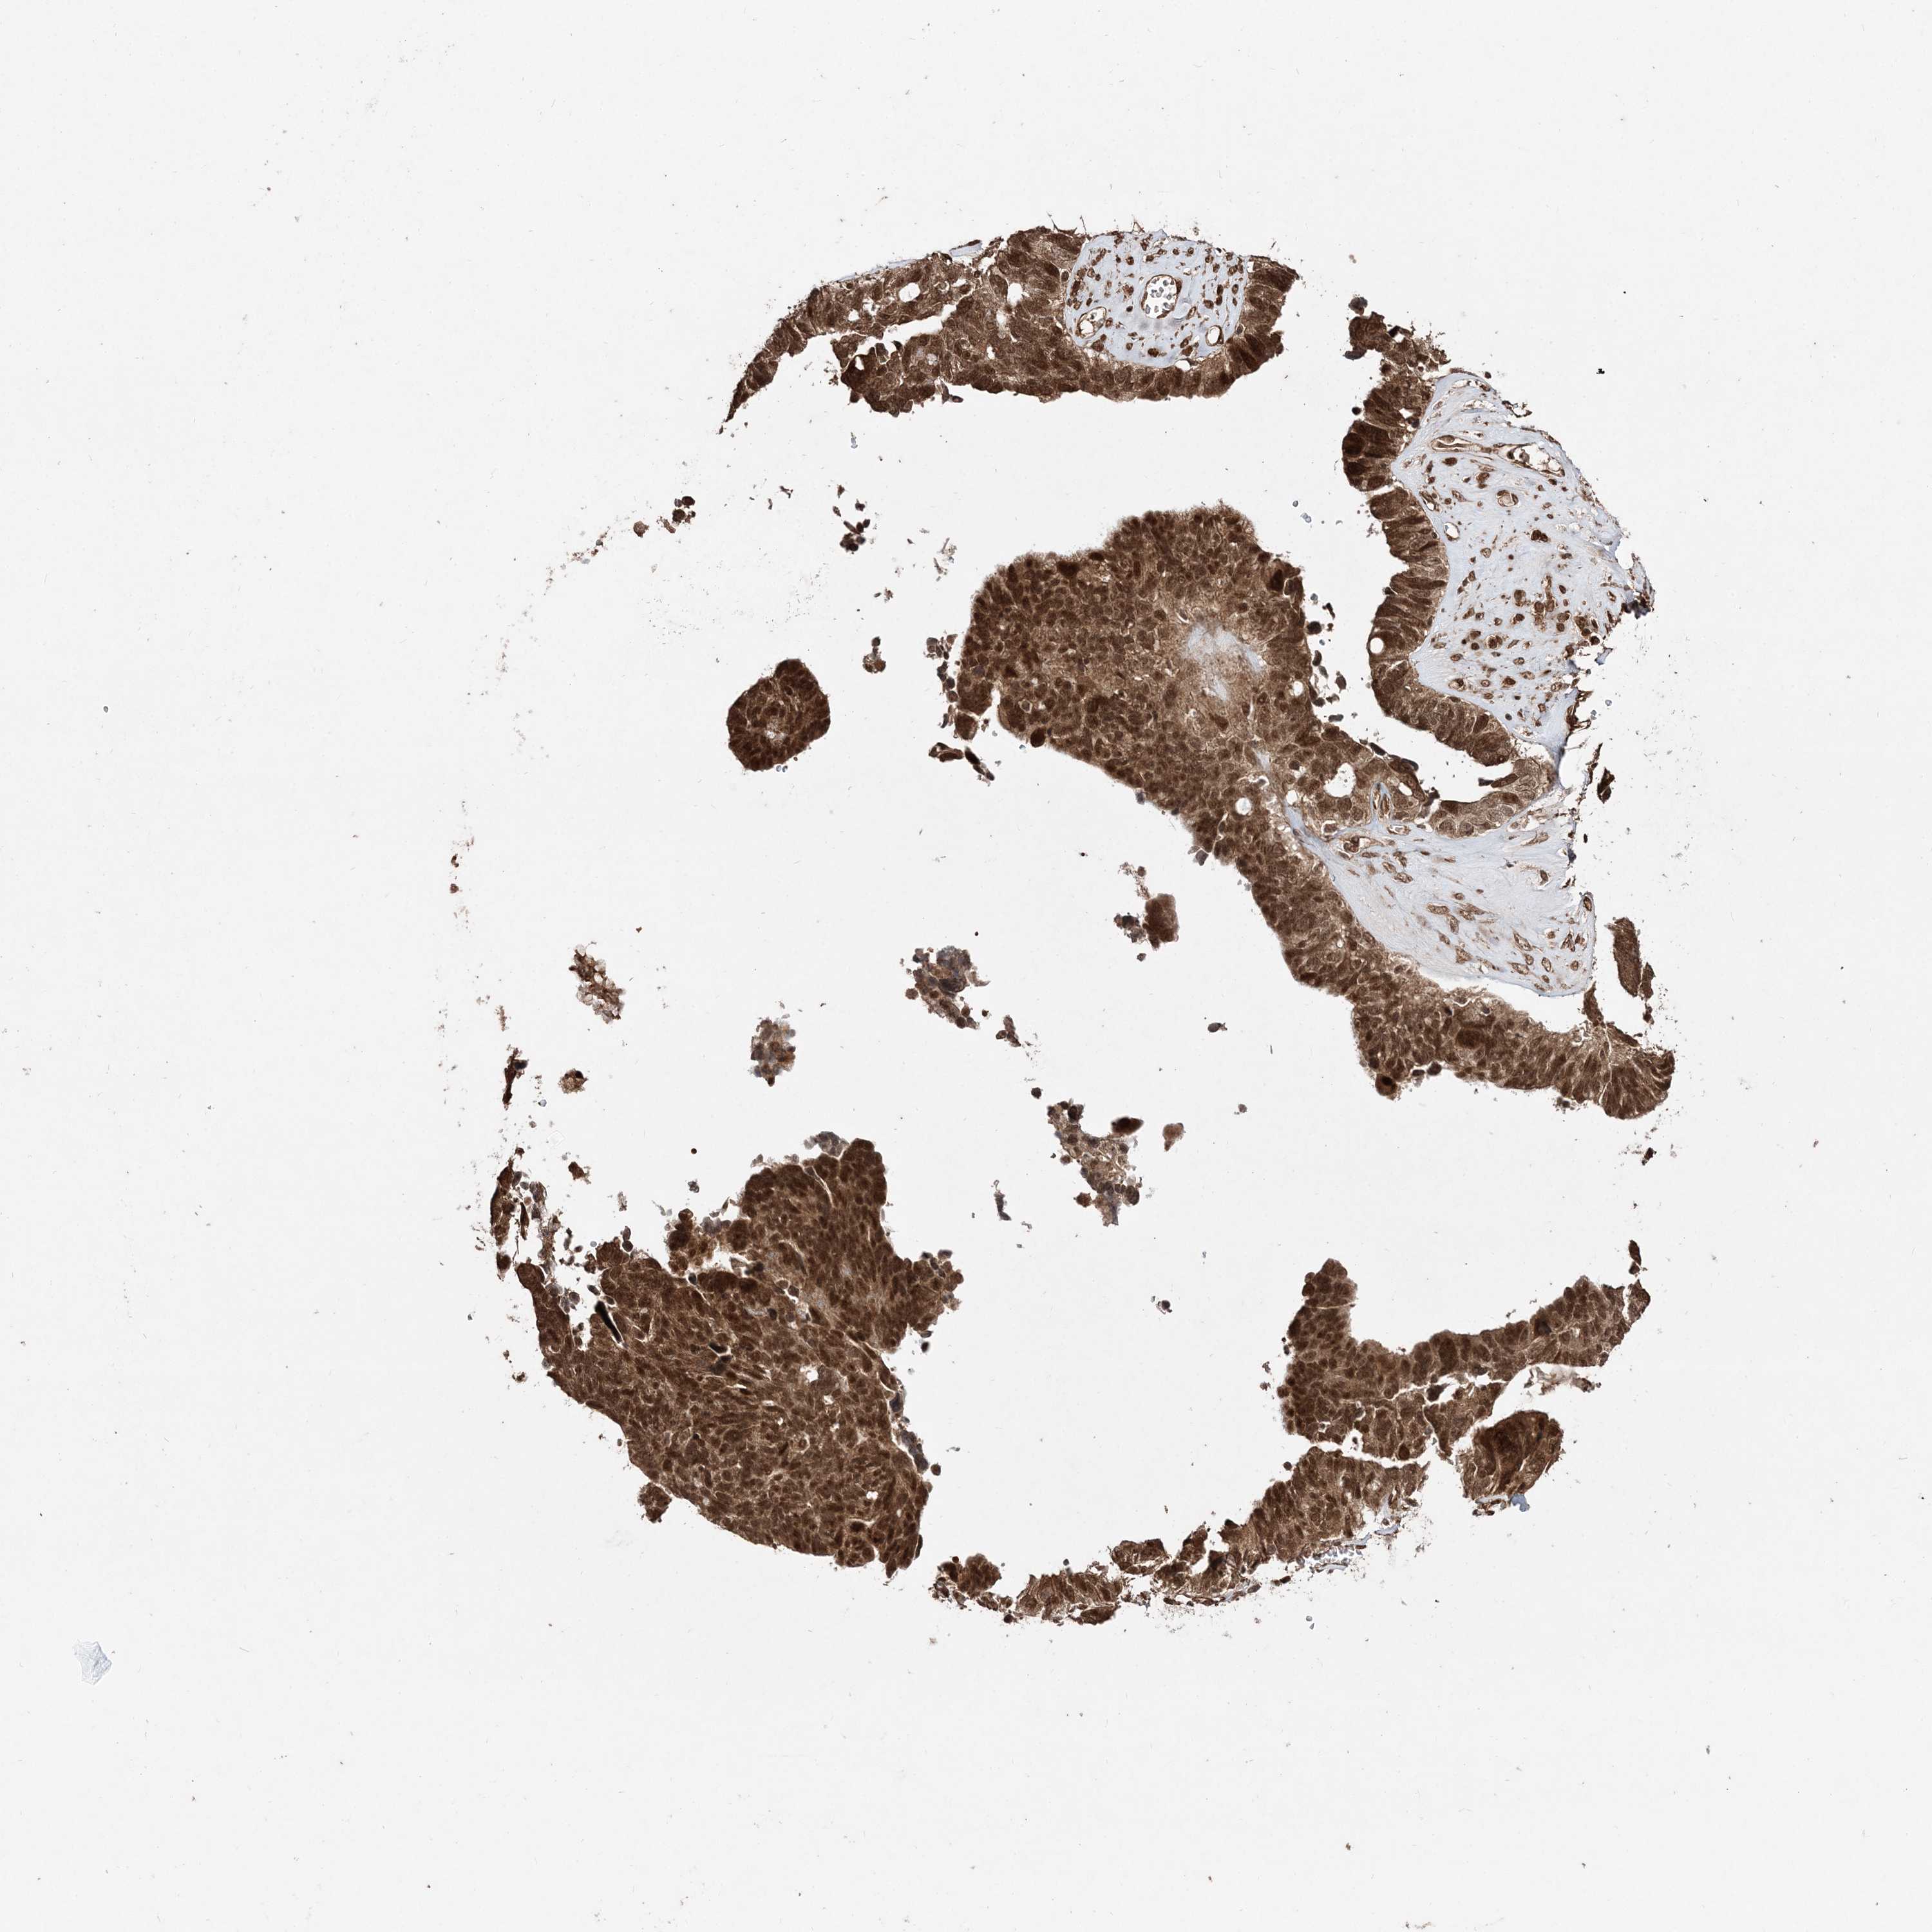

OVARIAN CANCER - Protein expressioni

A mouse-over function shows sample information and annotation data. Click on an image to view it in a full screen mode. Samples can be filtered based on level of antibody staining by selecting one or several of the following categories: high, medium, low and not detected. The assay and annotation is described here.

Note that samples used for immunohistochemistry by the Human Protein Atlas do not correspond to samples in the TCGA dataset.

Antibody stainingi

Antibody staining in the annotated cell types in the current human tissue is reported as not detected, low, medium, or high, based on conventional immunohistochemistry profiling in selected tissues. This score is based on the combination of the staining intensity and fraction of stained cells.

Each image is clickable and will lead to virtual microscopy that enables deeper exploration of all samples and also displays staining intensity scores, fraction scores and subcellular localization as well as patient and tissue information for each sample.

Antibody HPA035048

Antibody HPA035049

Carcinoma, NOS